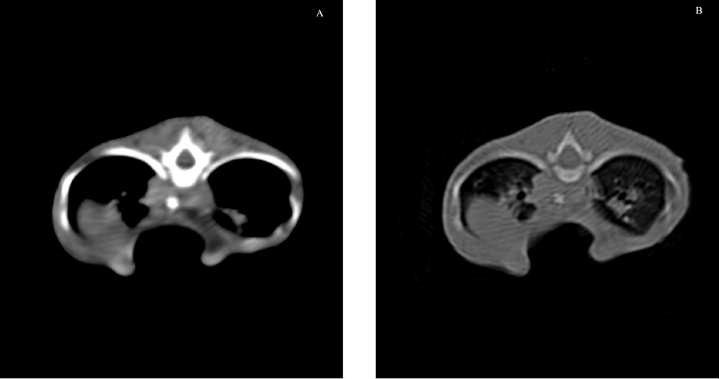

One month later, the kitten weighted 550 g and presented again for intermittent tachypnea, needing oxygen administration, and exercise intolerance. A preoperative CT was performed to evaluate the exact position of the intrathoracic structures and to assess safe corridors for the needle passage. CT was performed using a 20 slice TC scanner (Siemens® Somatom Sensation Open, Munich, Germany) with a 140 Kw and 150 mAs technique, in the awake patient, using a Plexiglas “mouse trap” (VetMouse trapTM) to restrain the animal. Only basal scans were obtained with 2 mm slice thickness, using 0.5 seconds rotation time. CT confirmed radiographic findings, adding more details (Fig. 3). Tomographic images revealed a complete dislocation of the heart into the left hemithorax, with complete atelectasis of the caudal portion of the cranial left lung lobe and partial atelectasis of the caudal left lobe near the hilum. The heart and the tracheal bifurcation were dislodged cranially compared to the normal anatomical position. The aortic arch was completely left-placed, together with the heart, but properly positioned at the level of the aortic hiatus. The caudal vena cava was dislocated to the left, resulting in a more central position, exactly interposed between the 12th vertebral body and the xiphoidal cartilage apex. The caudal vena cava and the aorta completely occupied the narrowed diaphragmatic portion of the thorax at the level of the xiphoid cartilage.

Fig. 3. Longitudinal reconstruction from CT scan. Notice the close relationship between the xiphoid process and the ventral aspect of the vertebral column.

Fig. 7. Transverse CT scan of the cat’s chest at the level of the xiphoid process, soft tissue window view (A), and bone window view (B).

The cat in this report was 3 months old and, based on the pectus severity index, had a severe pectus excavatum; therefore, an external splinting technique with a 3D-printed cast, customized on the base of CT images was chosen. CT scan was useful to better assess skeletal deformities, anomaly of the intrathoracic structures, and safe corridors for the needle passage. Moreover, CT was fundamental to design the splint. Five sutures were applied, the most caudal three being gradually pulled outward the concave part of the sternum and the other two directly ligated to the splint. The decision to surgically approach the seventh sternebra and xiphoid process to place the corresponding suture under direct vision was taken based on the result of the CT scan. CT images showed a close relationship between the seventh sternebra and the xiphoid process (Fig. 7), with the aorta and caudal vena cava occupying most of the thoracic space, making blind passage of the needle too risky. With this approach, the skeletal segment could be grasped and pulled ventrally, increasing the space for a secure passage of the needle. There were no surgical complications such as organ laceration or puncture, nor postoperative complications such as re-expansion pulmonary edema. The concern of the development of the re-expansion pulmonary edema, based on the sudden increase of the intrathoracic pressure due to the correction of the sternal concave deformity, lead the authors to the decision to gradually correct the sternal deformity. In this way, the increase in intrathoracic pressure and, therefore, lung re-expansion occurred little by little, reducing the risk for this complication. For these reasons, the sutures were gradually tightened during the first 2 weeks in response to the skeletal development of the kitten, and then kept in place for further 2 weeks to allow consolidation. The use of an electrician terminal block applied to the ventral part of the splint between the two rows of holes for the passage of the sutures perfectly fit this purpose. These locking clips allowed holding the sutures in position without the need to untie them each week.